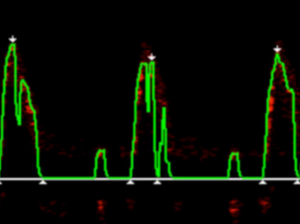

- In Run Mode, ensure the green line lies as close to the waveform edge as possible. If this begins to look ‘ragged’ the probe may not be fully focused. See ‘inadequate signals’ below.

- Ensure the white triangles fall at the base of the flow waveform and not consistently wide of this base since this could indicate the probe is not optimally focused.